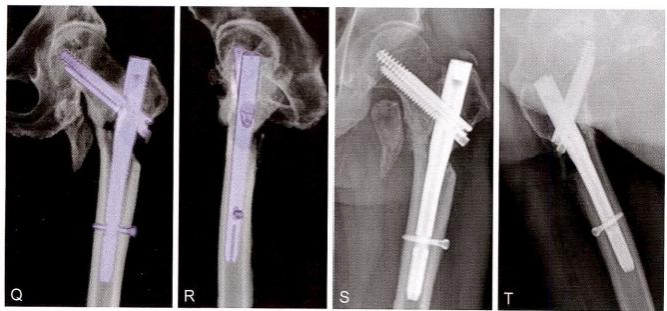

图9-22 ( 续 )G 、H. 闭合复位获得良好对线之后,微创导入钢丝,准备捆扎收拢小转 子骨块;I. 头髓钉手术之后,收紧小转子钢丝,但捆扎在髓内钉主杆上。为了避免干 扰骨折愈合,将其拆除;J 、K 、L. 术毕透视正位、侧位和前内侧斜位,示内芯螺钉拧 紧,远侧交锁螺钉打入在动力位;M 、N. 术后第5天拍片,示环周骨皮质缺损很多;O 、P. 术后三维 CT 显示仅前内下角约1/6的环周皮质相互抵住

图9-22 ( 续 )Q 、R.三维CT透明处理显示头髓钉内固定位置良好,髓内钉充满髓腔, 消除了髓内钉的摆动(雨刷效应);S 、T. 术后7个月,透视示股骨颈无短缩,内侧股 骨距愈合良好,外侧壁也出现骨桥连接。注意:与术后即刻相比,交锁螺钉上移